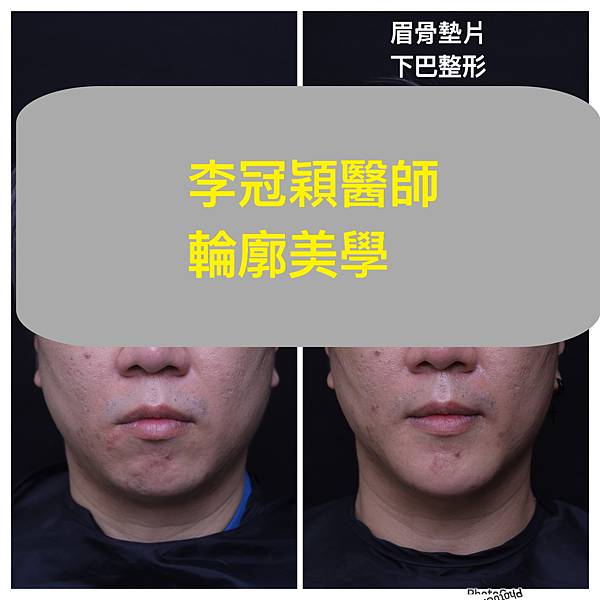

(男生範例)

輪廓在東方臉型是相當薄弱的一部分,只有整鼻子並不足以代表輪廓的到位,相反的只整鼻子可能會很突兀。下巴的後縮及過短在下臉部對於臉型平衡影響至大。

一張臉,除了對稱最重要的就是平衡,我們常聽到黃金比例或是應有比例,也就是表示臉部每一個部位都是有一定的相互角色達到平衡。下臉部的下巴,在東方人常常是後縮及過短,而且相對中臉顴骨較寬,所以往往失衡比例。因此東方臉型在整形手術中有一定比例的墊下巴或中臉削骨以達到平衡臉型。下巴短缺後縮,依程度不同而有不同的整形手術。